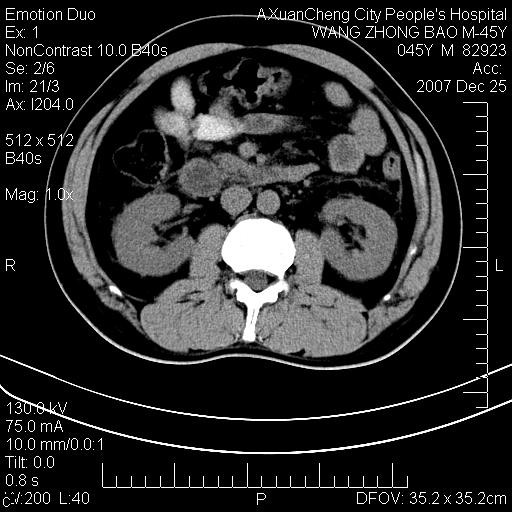

以下是引用qiuleiyu在2007-12-25 18:14:00的发言:[br]胰腺增大,周边渗出改变,肾前筋膜明显增厚,示少量积液.胆囊壁毛糙,周边少许渗出,胆总管壁厚,异常强化,然扩张不明显.结合病程急短;考虑;胆管炎,胆囊炎,胆源性胰腺炎可能大,请结合实验室检查及随访.

以下是引用lisihao在2007-12-25 14:23:00的发言:[br]急性水肿型胰腺炎[br]依据:1、胰腺弥漫性肿大,边缘稍毛糙;[br] 2、双侧肾周筋膜增厚,尤以左侧为甚(重要征象)[br] 3、双侧后胸膜增厚(刺激性炎症);[br] 4、结合病史,查血尿淀粉酶应该可以确诊。